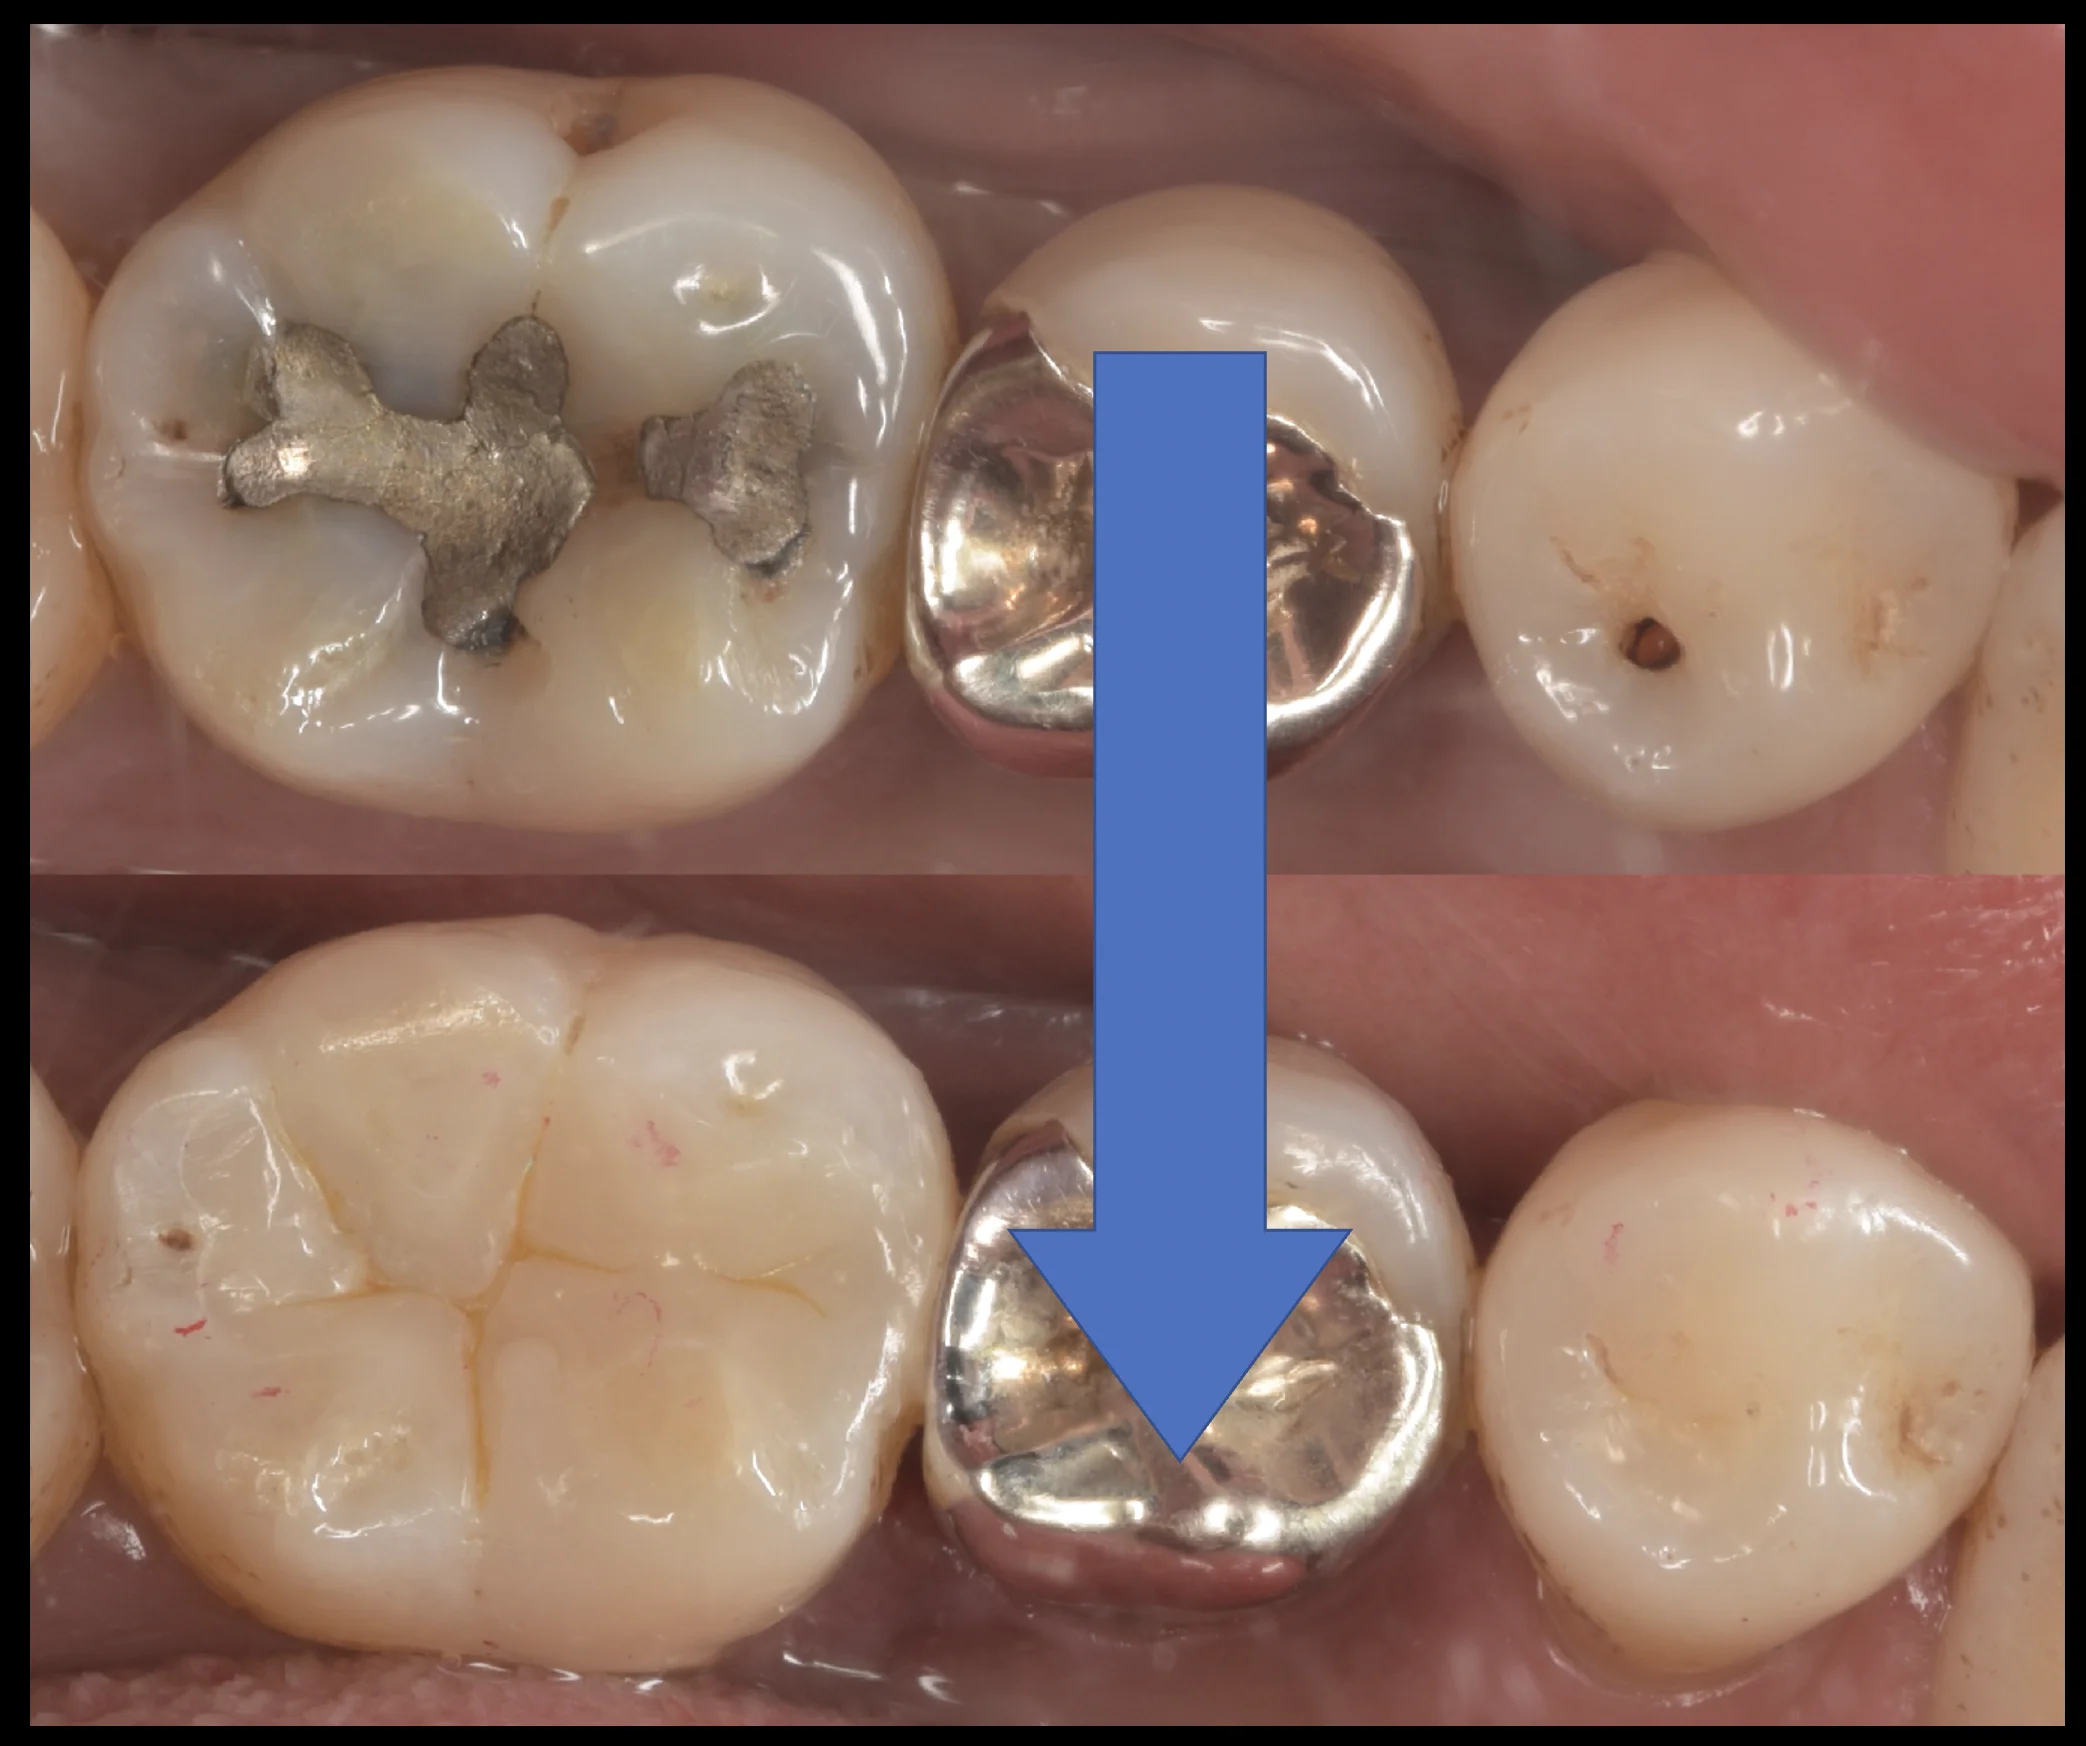

そして詰め終わったのがこちらになります。

いかがでしょうか?

違和感なく仕上げられたかと思います。

左側については詰めた部分がまだわかりやすくなっていますが、これは歯の乾燥が原因のため、1週間くらいして歯に水分が戻ると色としては違和感がなく合ってきます。

左はやや大きいですが、右の歯の虫歯は非常に小さいため、予後としては右の歯の方が相当に長期的に使えると予想できます。

実際歯の間に入っていない、右の歯のような虫歯は当院でも先代から20年以上持っているケースも珍しくないため個人的にはやはり小さければ小さいだけダイレクトボンディングで治療するメリットは大きいなと感じています。

治療の術前術後がこちらになります。

長時間の治療お疲れ様でしたヽ(゚∀゚)ノ パッ☆